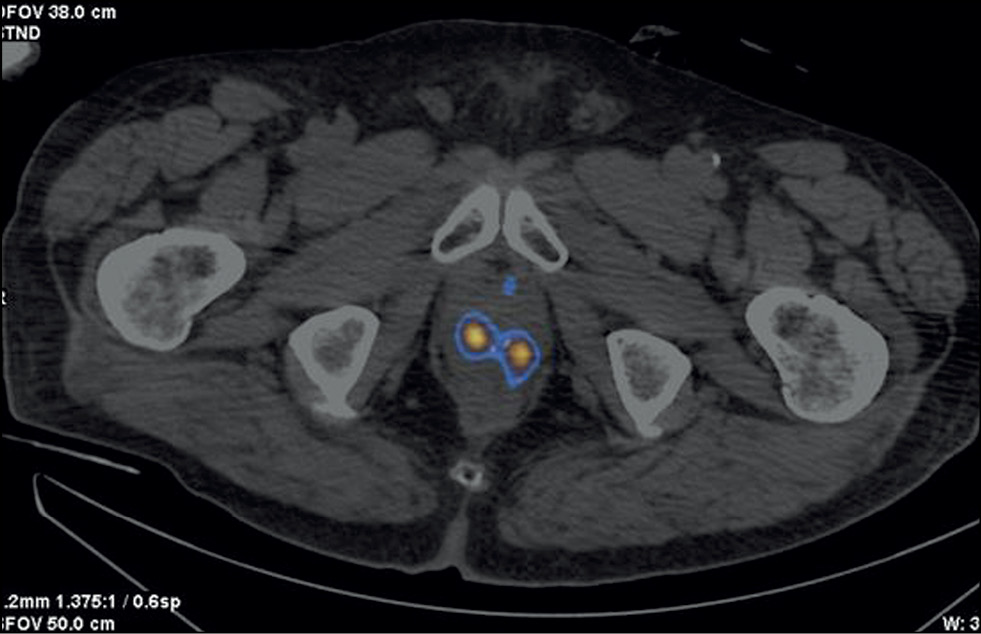

Patient Z., 79 years old, was admitted with diffuse prostatic hyperplasia. PSA level was 4.5 ng/mL. No abnormal lesions were found in the prostate tissue using ultrasound, TRUS, and contrast-enhanced MRI. SPECT/CT with 99mTc-HYNIC-PSMA revealed 15-mm3 sites of RP accumulation in the prostate tissue (Figure 3). Because rectal amputation made US-guided prostate biopsy impossible, a targeted CT-guided biopsy was performed pararectally. A morphological diagnosis was adenocarcinoma, Gleason 6 (3 + 3).

Fig. 3. Patient Z., 7 years old, SPECT/CT with 99mTc-HYNIC-PSMA: Sites of radiopharmaceutical accumulation in transitory zones of both lobes at the border of the middle third and the apex of the prostate gland.

In this case, two problems were revealed: an unknown cause of increased PSA over time and the inability to perform a targeted prostate carcinoma biopsy under US guide. Both problems were successfully resolved using hybrid SPECT/CT with 99mTc-HYNIC-PSMA followed by CT-guided RP accumulation site biopsy, and precision brachytherapy was performed with a smaller number of 125I microsources due to the SPECT/CT pattern.